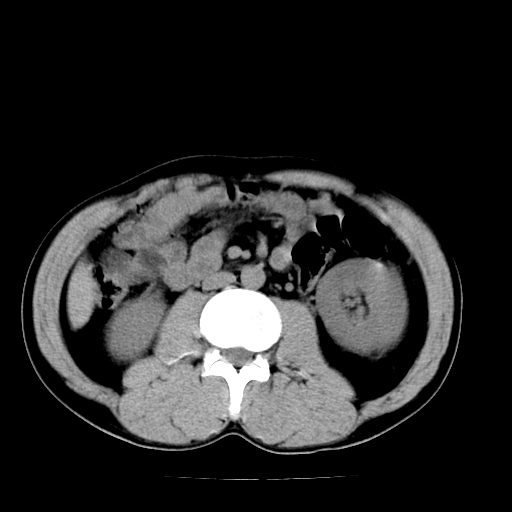

以下是引用天南地北在2007-4-30 13:36:00的发言:[br]支持慢性胰腺炎伴有假性囊肿

以下是引用andymaomao在2007-4-30 14:28:00的发言:[br]支持:1.慢性胰腺炎并假性囊肿形成可能;[br] 2.左肾形态稍增大,旋转不良。